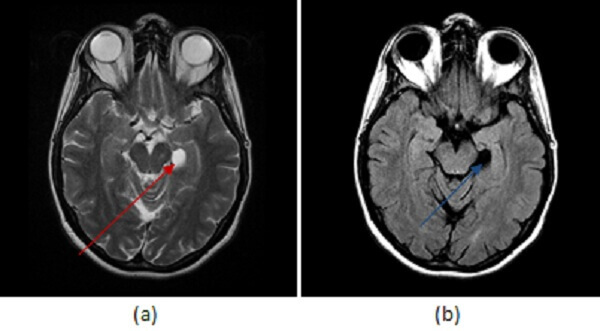

Figure 1: (a) axial T2 demonstrates a circumscribed T2 hyperintense lesion (red arrow) without increased FLAIR signal (b, blue arrow) or contrast enhancement (c, green arrow).

Some benign congenital variants of the limbic system can mimic real pathology and it is important to be aware of such variations to avoid mistaking them for disease. For example, choroidal fissure cysts are benign extraaxial cysts (typically arachnoid or neuroepithelial) that arise within the choroidal fissure, a c shaped cleft that separates the medial border of the temporal lobe from the diencephalon. Choroidal fissue cysts are incidental asymptomatic findings that require no further imaging or evaluation. The differential diagnosis includes low grade cystic neoplasms such as dysembryoplastic neuroepithelial tumor (DNET) or a ganglioglioma, but former typically has a soap bubble appearance, the later may have a mural nodule or enhance and both should have some degree FLAIR signal abnormality.

A simple cystic lesion in the hippocampal sulcus without enhancement or FLAIR signal abnormality is a choroidal fissure cyst and should not be mistaken for limbic system pathology.